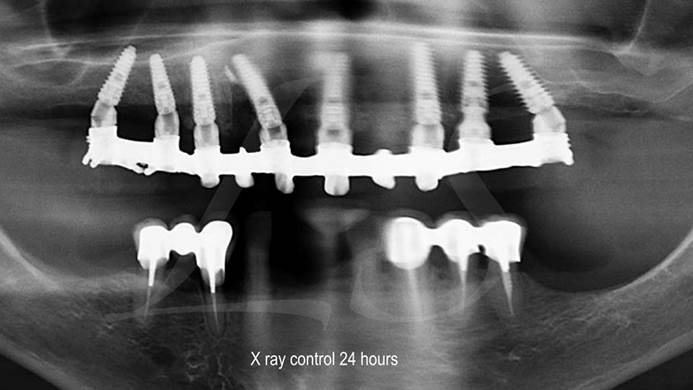

Clinical case: Full-arch implant treatment with immediate loading & extraction implantation

- Courtesy of Dr. Laurent Sers, France -

AnyRidge, R2GATE, guided surgery, Dr. Laurent Sers, immediate loading, maxilla

AnyRidge implant system, R2GATE, Digital prosthesis